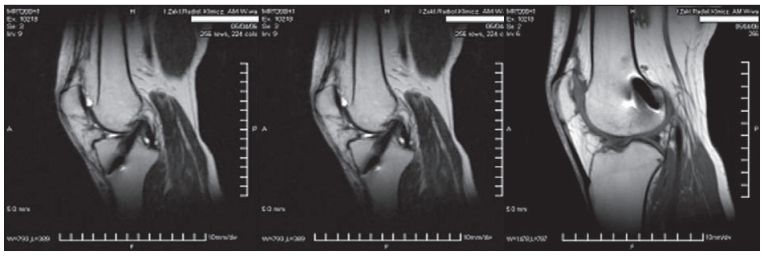

Obraz

Badanie MR 6 tygodniach od zabiegu – (A) widoczny kanał piszczelowy, (B) część śródstawowa więzadła, (C) kanał udowy